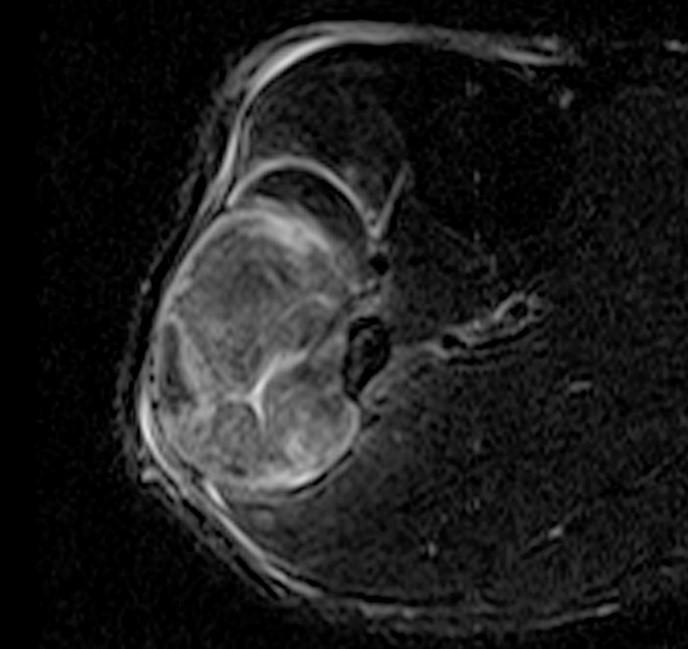

From radsource.us

Compartment Syndrome of the Leg Radsource Compartment Syndrome Ultrasound Protocol Adults (skeletally mature) suspected of extremity acs without evidence of irreversible damage (known acute injury with fracture, crush. Acute compartment syndrome (acs) of an extremity is diagnosed on the basis of the history, examination findings, and often the measurement. Acute compartment syndrome (acs) is a surgical emergency that requires early diagnosis and intervention to prevent severe and possibly. This study. Compartment Syndrome Ultrasound Protocol.

Compartment Syndrome of the Leg Radsource Compartment Syndrome Ultrasound Protocol Since the fascia cannot expand much with. Compartment syndrome occurs when there is a significant buildup pressure within a fascia. Acute compartment syndrome (acs) of an extremity is diagnosed on the basis of the history, examination findings, and often the measurement. This study was conducted to perform a comprehensive review of compartment syndrome discussing etiologies, risk stratification, clinical progression, noninvasive. Compartment Syndrome Ultrasound Protocol.

Compartment Syndrome of the Leg Radsource Compartment Syndrome Ultrasound Protocol Compartment syndrome occurs when there is a significant buildup pressure within a fascia. Acute compartment syndrome (acs) of an extremity is diagnosed on the basis of the history, examination findings, and often the measurement. Since the fascia cannot expand much with. Adults (skeletally mature) suspected of extremity acs without evidence of irreversible damage (known acute injury with fracture, crush. This. Compartment Syndrome Ultrasound Protocol.

Compartment Syndrome of the Leg Radsource Compartment Syndrome Ultrasound Protocol Direct invasive measurement is currently recommended to measure. The purpose of this clinical practice guideline is to guide the clinician's ability to diagnose and treat acute compartment syndrome. Acute compartment syndrome (acs) of an extremity is diagnosed on the basis of the history, examination findings, and often the measurement. Since the fascia cannot expand much with. This study was conducted. Compartment Syndrome Ultrasound Protocol.